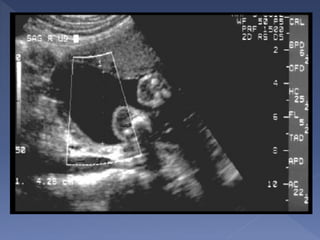

 Appropriate plane

Landmarks:

o Spine + rib

o Stomach

o Part of portal

vein

o Picture should

be as round as

possible

 The single most important measurement

to make in late pregnancy

 It reflects more of fetal size and weight

rather than age.

 Serial measurements are useful in

monitoring growth of the fetus.

 AC measurements should not be used

for dating a fetus.

 It is also a mandatory measurement.

Plane

 The best plane is the one in which the portal

vein is visualized in a tangential section.

 The plane in which the stomach is visualized

is also acceptable.

 The outer edge of the circumference is

measured

 On screen computer-generated elliptical

measurements probably yield the best

results